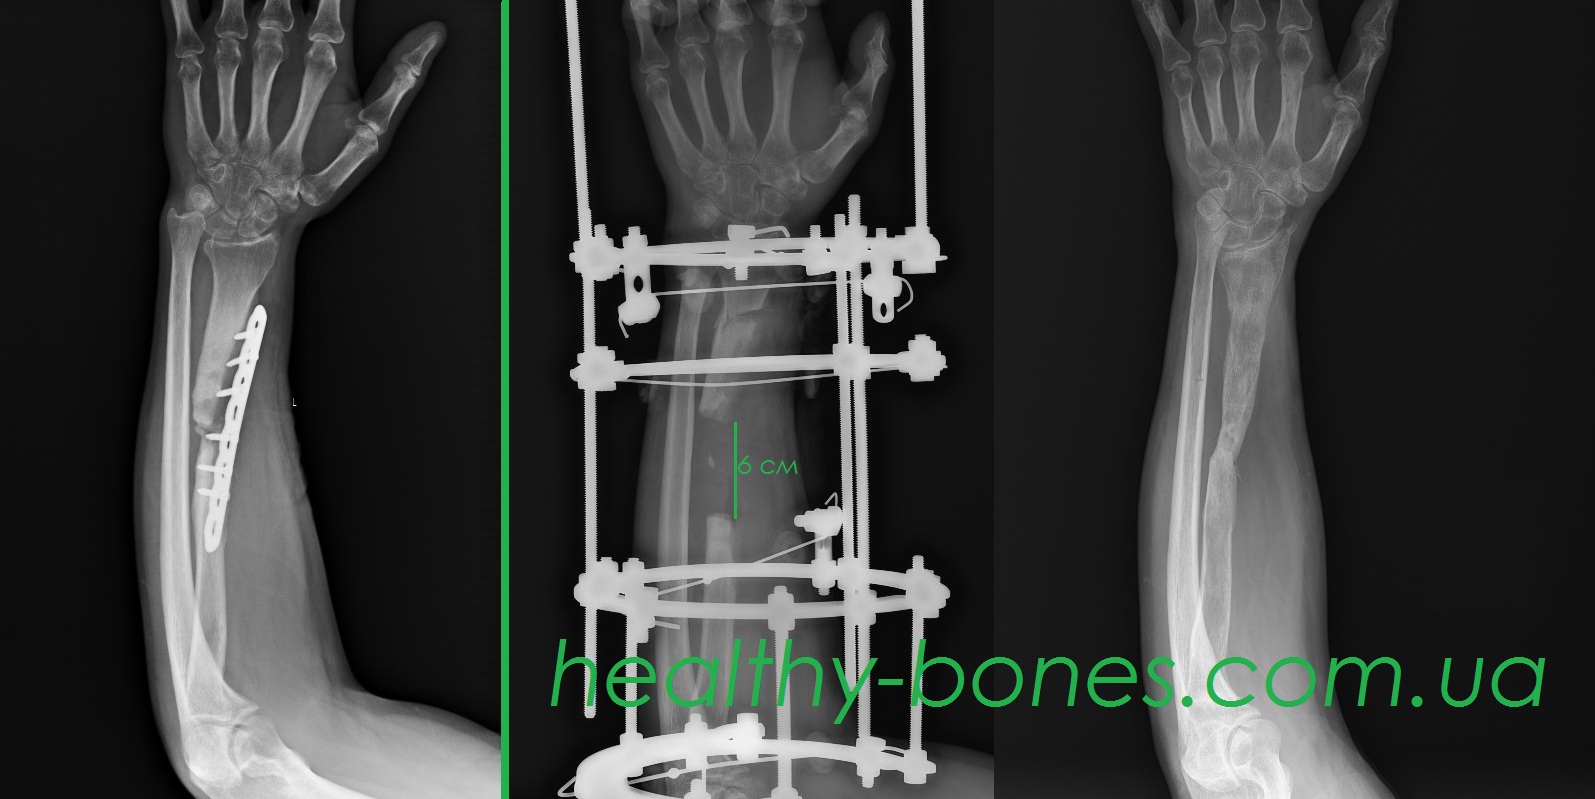

Ми провели етапне хірургічне лікування. Під час першого етапу було встановлено, що променева кістка змертвіла протягом 6 см. Мертву ділянку кістки було резецовано. Лікування проводилося за методом Ілізарова.

В результаті нашого лікування остеомієліт був ліквідований, і через 10 місяців від початку лікування була повністю відновлена ​​цілісність променевої кістки.